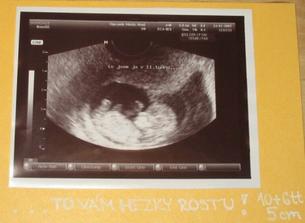

SRPŇÁTKA 2007 - fotky UTZ

album věnované mimískům, které se narodí v srpnu 2007 a jejich maminkám ze "Společného termínu SRPEN"